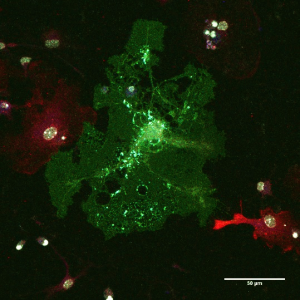

Το πρόγραμμα CLLon στοχεύει στην κατανόηση των διαδικασιών που σχετίζονται με το Β κυτταρικό υποδοχέα (ΒΚΥ), οι οποίες συμβαίνουν κατά τη φυσική εξέλιξη της Χρόνιας Λεμφοκυτταρικής Λευχαιμίας (ΧΛΛ) και συνεισφέρουν στην οντογένεση και την πρόοδο της νόσου μέσω της εφαρμογής ανοσογενετικών και λειτουργικών μελετών του…